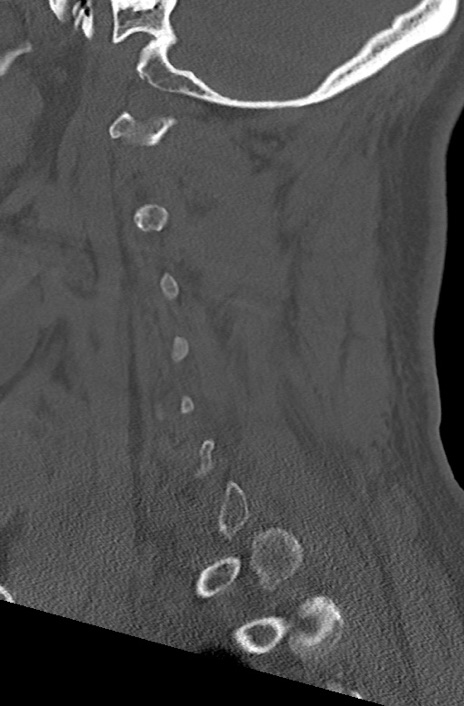

頚椎CT

冠状断像